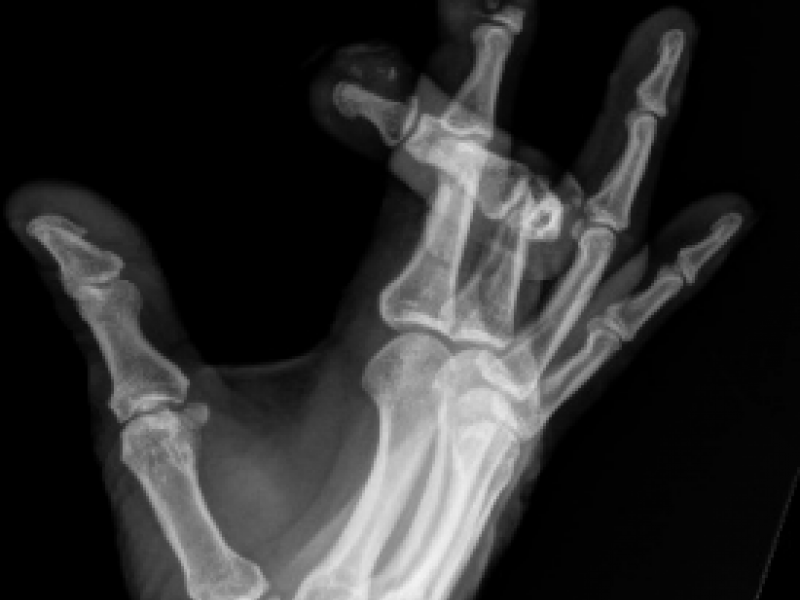

What's the diagnosis? By Dr. Becca Fieles

A 27 year old male with no significant past medical history